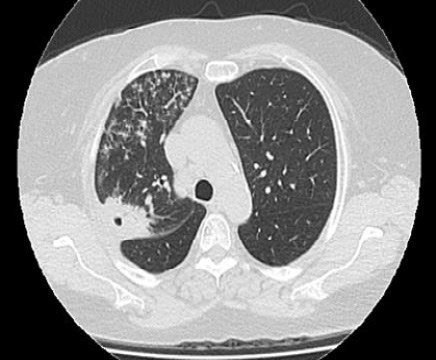

Paciente femenina de 59 años con antecedentes de ex tabaquista de 20 paquetes año, EPOC Gold 2 B, neumonías a repetición, bypass gástrico, alérgica a ampicilina y sulfonamidas. Padre fallecido de cáncer de pulmón. Consultó al servicio de urgencias por tos seca, disnea clase funcional II y registros subfebriles de 5 días de evolución. Le realizaron test para SARS-CoV-2 con resultado negativo y le indicaron tratamiento sintomático. Luego de una semana volvió a consultar por la persistencia de los síntomas y agregó fiebre de hasta 38, 5°C. La radiografía de tórax evidenció una opacidad en la base pulmonar derecha, por lo que fue medicada con claritromicina. Luego de una semana, la paciente persistió febril y le adicionaron levofloxacina. Tras cumplir el tratamiento antibiótico, no hubo mejoría del cuadro clínico por lo que se decidió su hospitalización. La tomografía computada de tórax (TC) evidenció una opacidad de aspecto consolidativo de disposición yuxta cisural, de bordes irregulares y cavitación central que comprometía el segmento posterior del lóbulo superior derecho, opacidades pseudonodulares en lóbulo medio y árbol en brote comprometiendo extensamente el campo pulmonar derecho. (Figura 1) Los exámenes de laboratorio encontraron reactantes de fase aguda elevados, perfil reumatológico negativo e IgE elevada como datos a destacar. La función renal fue normal y las serologías negativas. Se realizó lavado bronquio alveolar (BAL) sin hallazgos patológicos.

Consolidación yuxta cisural, de bordes irregulares y cavitación central en el lóbulo superior derecho y árbol en brote comprometiendo el campo pulmonar derecho.